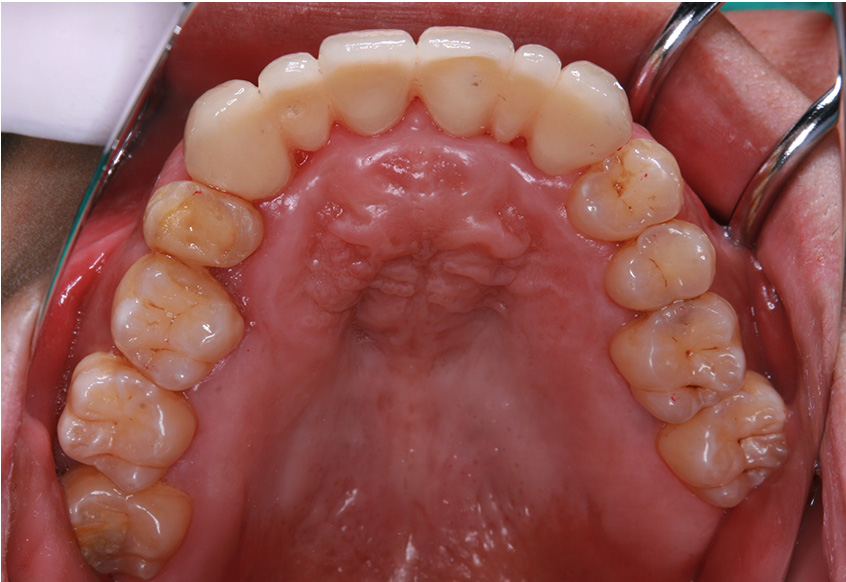

最初のお口の中 ワイヤー装着して治療を開始

-

治療開始後3ヵ月経過すると、前歯の隙間や全体の乱れが減ってきました。口笛が吹けるようになったとのことです。

最初のお口の中 治療開始3ヵ月後

6ヵ月経過すると、矯正治療を終了し、前歯に被せ物の治療を行いました。

最初のお口の中 2025/3/22

被せ物装着

当院では、歯並びが気になる人に対して、矯正治療を行っています。また今回の症例のようにワイヤーを用いた治療からマウスピース矯正治療も行っておりますので、スタッフにお声かけください。

| 患者属性 | 30代男性、歯科恐怖症 |

|---|---|

| 主訴 | 上の前歯の歯並びを整えたい |

| 診断 | 歯列不正、う蝕歯 |

| 矯正装置 | 矯正ブラケットとワイヤー |

| 治療期間 | 約6ヵ月 |

| 通院回数 | 8回 |

| 治療費 | 矯正:基本料金(220,000円)+調整料(5,500円×6回)、補綴治療:72,600円、費用は税込 |

| 治療内容 | 上顎側切歯を2本抜歯した後、上顎の歯にブラケットを装着し、ワイヤー、矯正用ゴムで歯の移動を行いました。その後、被せ物の治療を行って治療を終了しています。 |